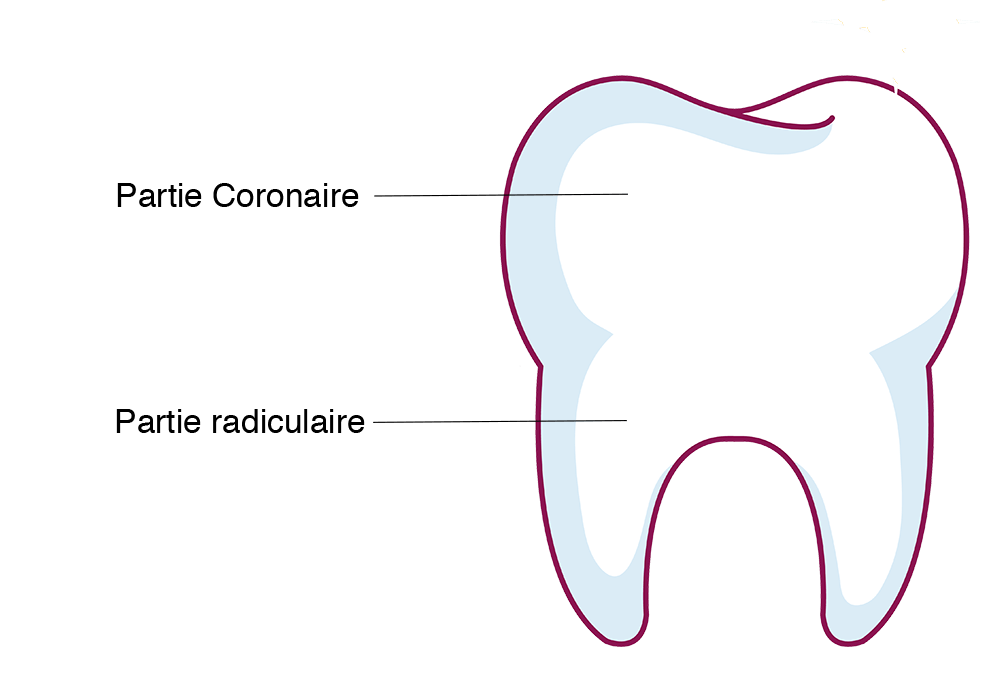

Pour comprendre ce qu’est un implant il faut d’abord comprendre l’anatomie d’une dent.

Une dent possède une partie radiculaire (les racines) et une partie coronaire (la couronne naturelle).

Quand une dent est abîmée on peut remplacer la partie du dessus par un élément prothétique par exemple une couronne artificielle en métal ou en céramique qui va s’appuyer sur la ou les racines naturelles de votre dent.

Si la dent est trop abîmée et quelle doit être extraite, il ne restera plus rien de la couronne ni de la racine. ll ne restera donc en fait que de la gencive et de l’os.